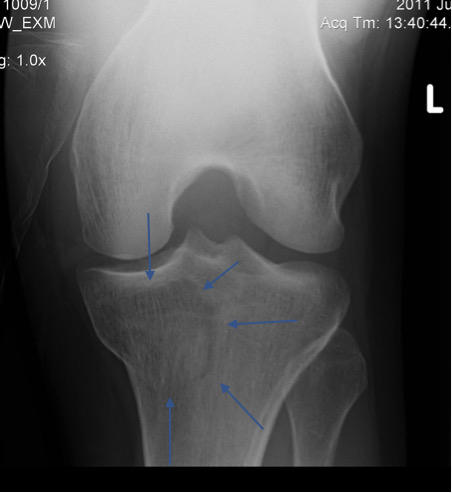

You don’t want to go wiggling a knee that has a tibial plateau fracture (as in the x-ray below) going on inside it. Indeed, if the x-rays show a fracture – bingo – job done. Sometimes though, plateau fractures are not well defined on x-ray, so follow up with CT. If there isn’t a fracture then go ahead and examine the patient.

If you think the ACL has gone, then you need to x-ray to rule out a tibial spine fracture as in the x-ray below. This is critical because ACL injuries should be mobilised early with aggressive physiotherapy prior to reconstruction, whereas the fracture should be immobilised and non-weight bearing on crutches prior to definitive imaging and orthopaedic review. Important difference.

Lesson 3 / When you see a Segond fracture, you know for sure that there is an ACL rupture.

What a little beauty this one is. You wiggle the knee, call it an ACL, get the x-ray, spot the Segond fracture, and then it’s a hi-five FIGJAM moment. Or else it’s your first week in the clinic, all the knees still feel the same, and then the x-ray saves you.

The fracture is seen quite easily in the x-ray below and is caused by rotational forces in which the lateral retinaculum produces a small avulsion fracture. The fracture in itself is irrelevant, but it just so happens that any twisting injury severe enough to create this fracture has already ruptured the ACL.